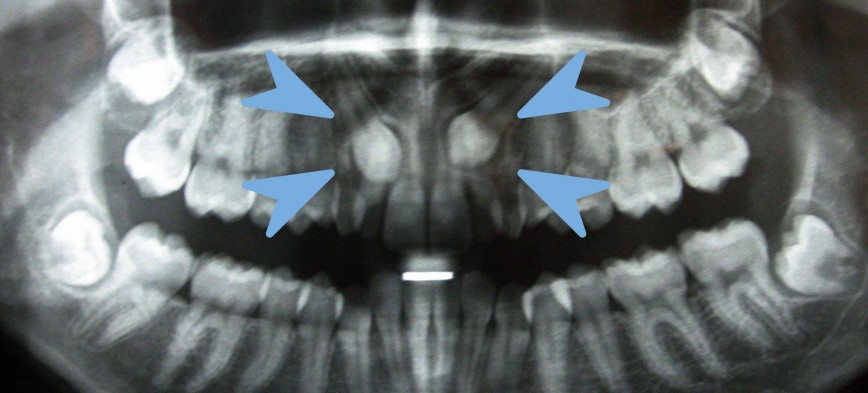

Casos Clínicos